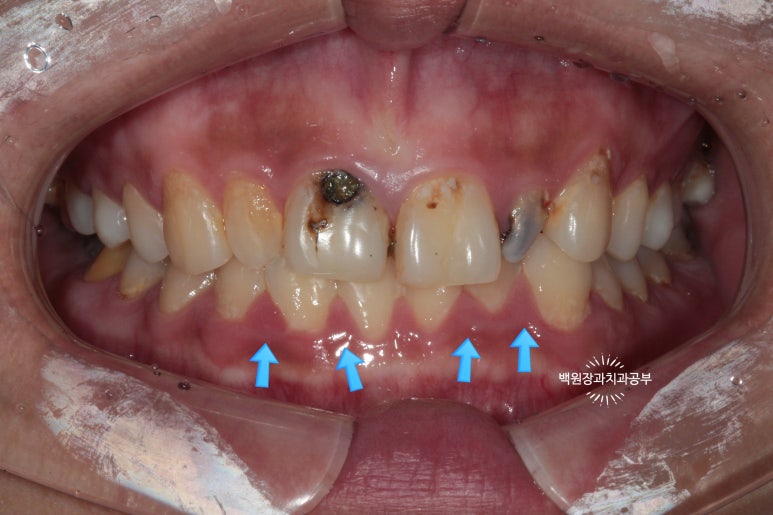

환자분은 당시에 흡연 하시는 상태였는데요, 그로 인해 치은염 (=잇몸 염증)도 심하여 꽤나 잇몸이 부어있는 것을 확인할 수 있었습니다.

화살표로 표시해 둔 치아와 치아 사이의 잇몸이 상당히 붉고, 붓기로 인해 모양이 둥그렇게 변한 것을 보실 수 있습니다. 전형적인 치은염/치주염 소견입니다. 심해지면 풍치가 됩니다.

사실 잘 인지가 안되어서 모르실수도 있어요! 저도 처음에는 그랬습니다. ㅎㅎ

치주과 전문의가 되니 잇몸 색만 봐도 잇몸 속에 치석이 있는지 알 수 있습니다. (저를 지도해주신 교수님의 말씀..ㅎㅎ)

치료 전/후 사진을 비교해 보실 때 차이를 느끼실 수 있을겁니다.